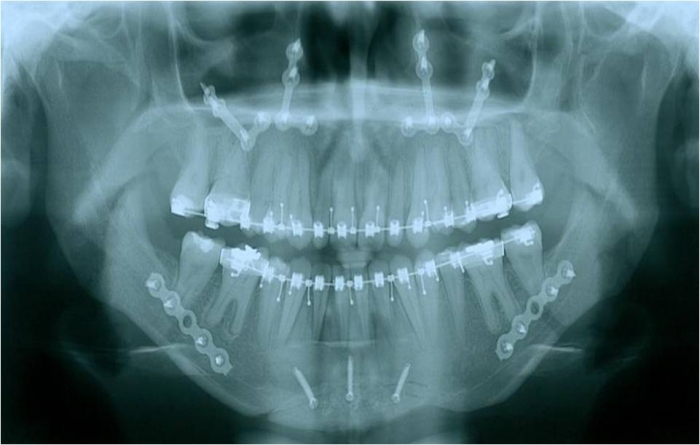

Rx após a cirurgia - Clínica Cliniface

Rx após a cirurgia